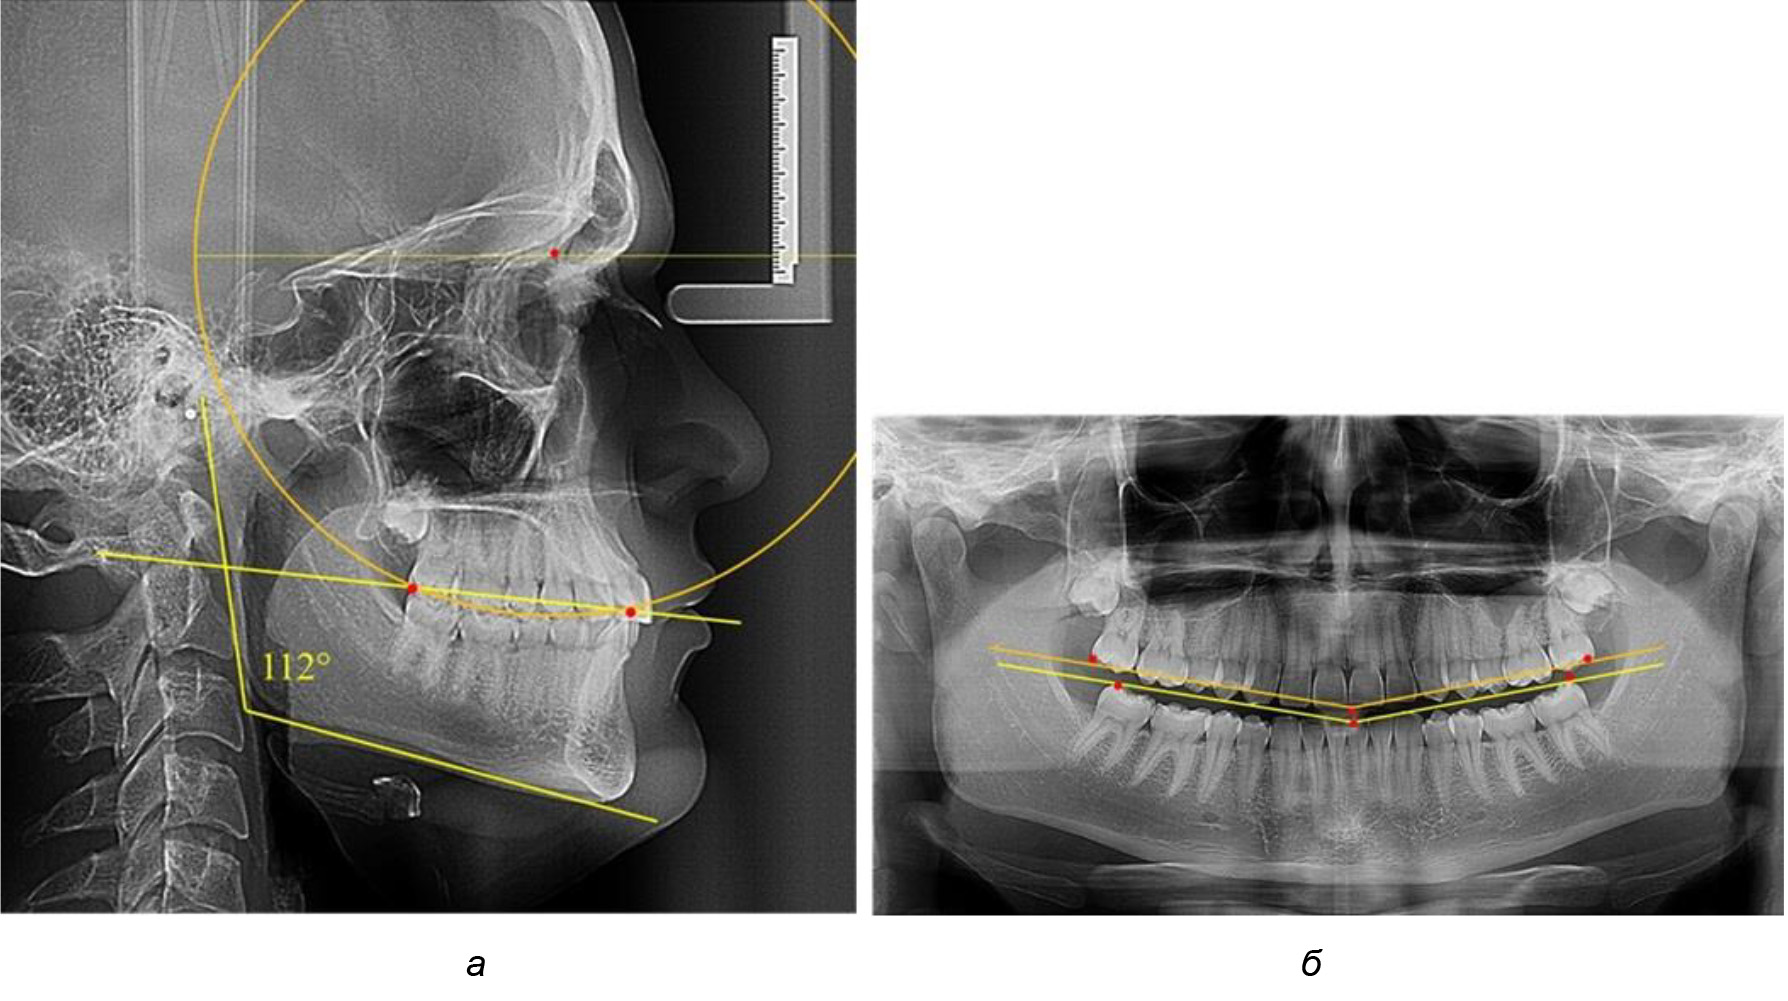

При анализе латеральных ТРГ устанавливали реперный окклюзионные точки в переднем и боковом отделе. Передняя точка устанавливалась на режущем крае нижнего медиального резца, которую в клинике ортодонтии обозначают как vPOcP. Дистальная точка второго нижнего моляра обозначалась как hPOcP. Измеряли расстояние между окклюзионными точками, что определяло сагиттальный размер окклюзионной линии. Использование программ PowerPoint позволило проводить окружность, проходящую по линии смыкания зубов через окклюзионные точки. Измеряли радиус окружности. Учитывая вариабельность размеров окклюзионной линии и радиуса окружности, определяли относительный показатель через отношение радиуса круга к длине сагиттального размера окклюзионной линии. Глубину окклюзионной кривой измеряли от точки наибольшей выпуклости до окклюзионной линии (рис. 1). На ортопантомограмме (ОПТГ) также соединяли окклюзионные точки правой и левой стороны и измеряли глубину окклюзионной кривой от точки наибольшей выпуклости до окклюзионной прямой линии. Результаты глубины кривой Spee сравнивали по данным ТРГ и ОПТГ.

Рис. 1. Метод определения кривой Spee на ТРГ (а) и на ОПТГ (б)

Рис. 2. Особенности кривой Spee на ТРГ (а) и ОПТГ (б) у людей с признаками вертикального роста